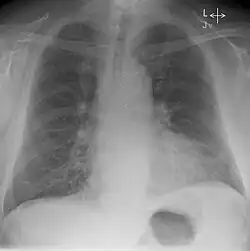

Kerley-Linien sind zarte Linien auf dem Röntgenbild der Lunge. Sie weisen auf pathologisch verbreiterte Alveolarsepten und Lymphgefäße der Lunge hin, am häufigsten verursacht durch eine Herzinsuffizienz. Auch Pneumonien, Lungenfibrose und eine diffuse Absiedlung von Tumorzellen in der Lunge (Lymphangiosis carcinomatosa) können zu sichtbaren Kerley-Linien führen.

Unterschieden wird zwischen feinen, langen Kerley-A-Linien eher in den oberen Lungenabschnitten und kurzen, waagerechten Kerley-B-Linien, die in den unteren Lungenabschnitten nahe der Thoraxwand im so genannten costophrenischen Winkel verlaufen (vorwiegend rechtsseitig). Kerley-C-Linien sind spinnwebenartige Linien über der gesamten Lunge.